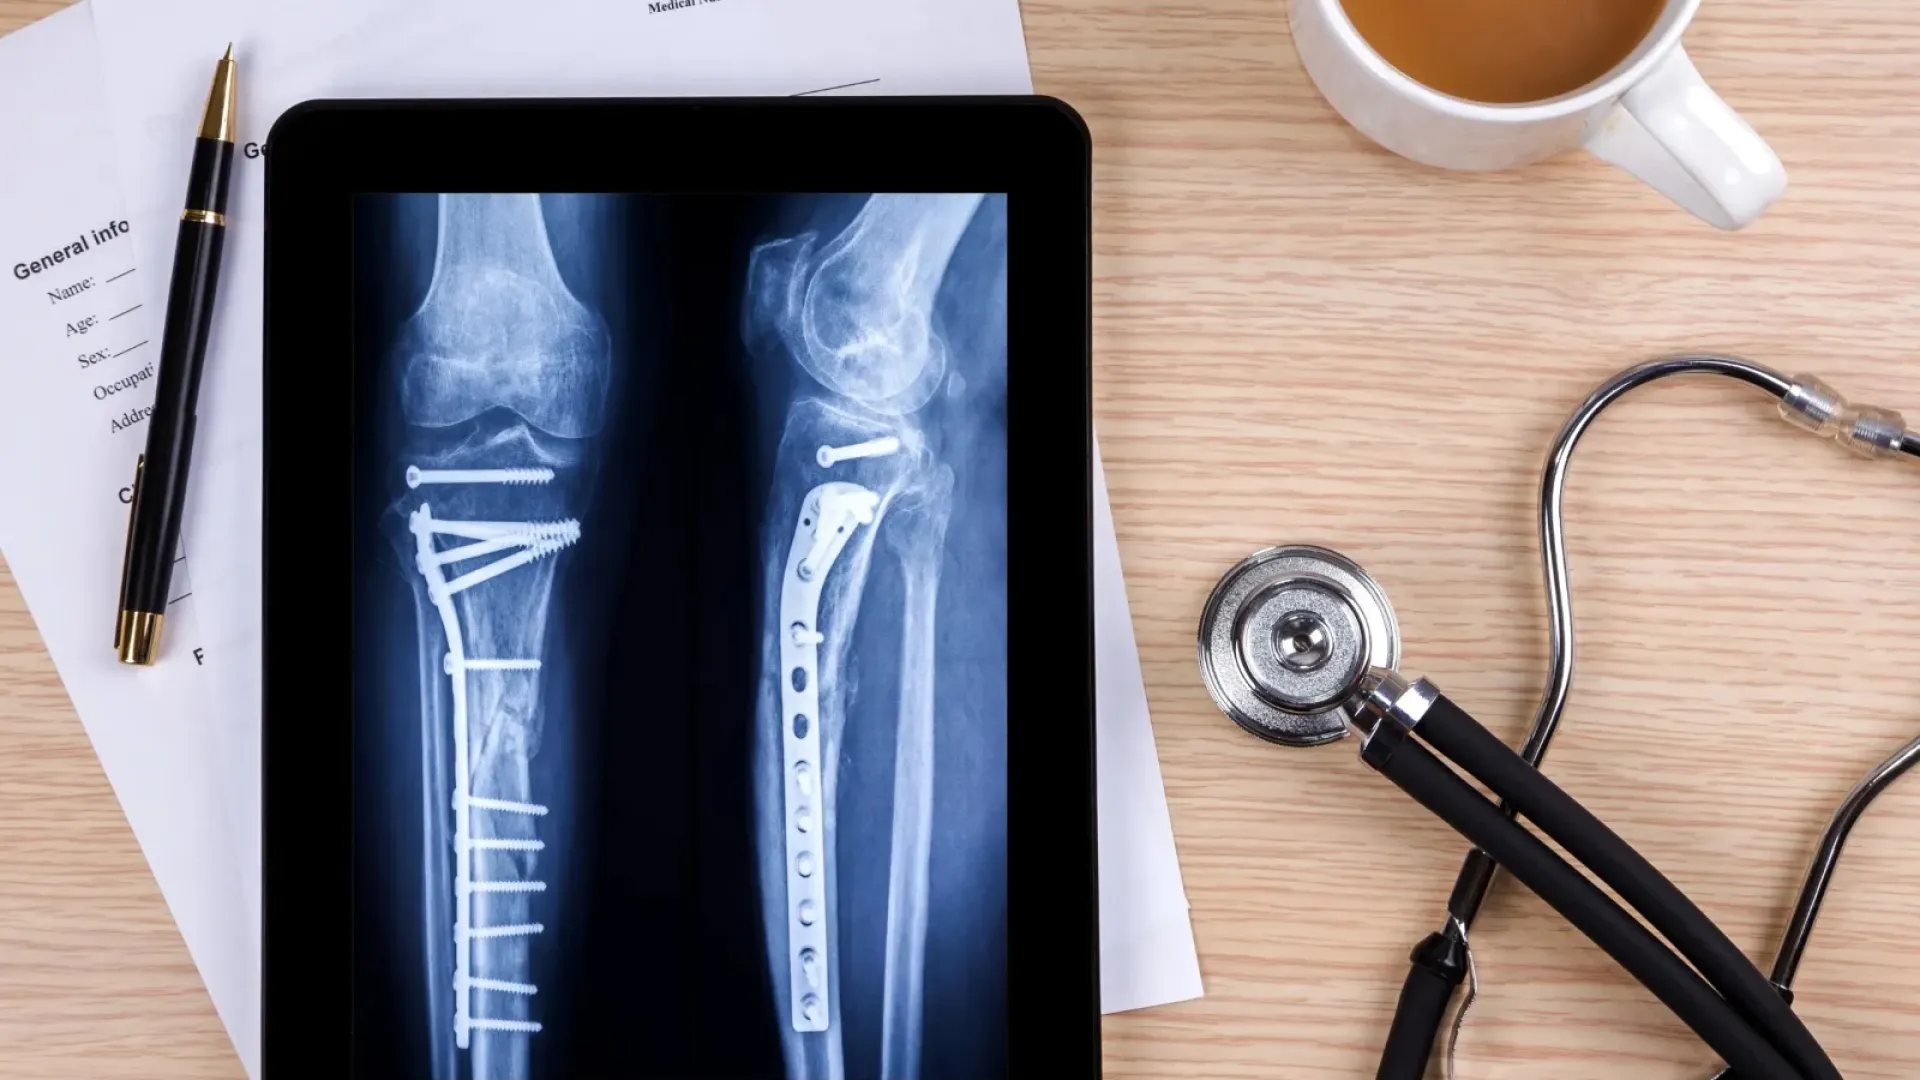

External fixation refers to a surgical operation that involves the use of screws, metal pins, and bars to stabilize and align the damaged bone. It is considered "external" since the metal pins are placed into the bone where it's attached to screws and bars outside the skin.

The Maxframe Autostrut is an external fixator device that utilizes a hexapod frame with two circular rings and six robotic struts. It works by following a computerized correction plan that automatically implements the length and angulation specified by Dr. Terrell. This integrated software allows him to record and track your progress so that he can adjust your treatment plan accordingly.

Furthermore, the Maxframe Autostrut is equipped with fully automated struts to deliver accurate and more frequent daily adjustments. So, instead of manually adjusting the braces, he can program the device to make the proper length adjustments to repair fractures and deformities efficiently.

External fixation works on different principles depending on the patient's condition and medical needs. For example, if the patient has a fracture, the surgeon may place an external fixator to stabilize the damaged bone as it heals to avoid malunion. It can also help reduce the pressure off of the healing bones and joints during movement.

But during limb deformities, an external fixator's main goal is to correct the abnormality using the principle called osteodistraction or distraction osteogenesis. The process involves cutting the deformed bone and then intentionally moving it apart (millimeter by millimeter) using a controlled device (external fixator), so new bone may fill the gap.